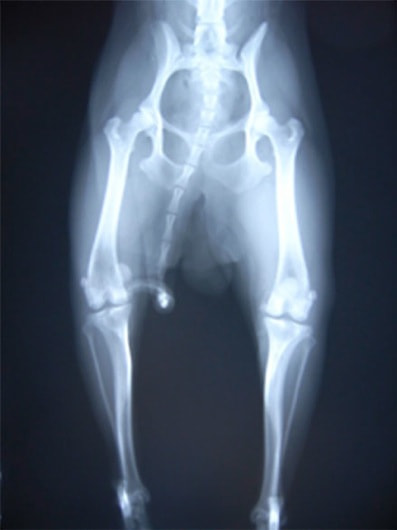

■ 症例24 キャバリア 7か月

左右膝蓋骨内方脱臼(左:グレードⅣ 右:グレードⅢ)

以前から左右後肢の跛行が認められ、整形外科学的検査・レントゲン検査により左右の膝蓋骨脱臼が認められた。症状が重度である左膝の膝蓋骨脱臼整復術を行った。外科手技は縫工筋及び内側広筋の解放、脛骨粗面の外側転位、滑車ブロック形造溝術、内外側関節方の縫縮を実施した。術後一か月時点で、左の膝蓋骨は安定しており経過は良好である。

本症例は成長期における重度の膝蓋骨脱臼であり、術後の再発の可能性もあるため、経過をしっかりと観察していく必要がある。また、今回手術を実施していない右膝に関しても経過を観察し、手術を検討していくこととする。